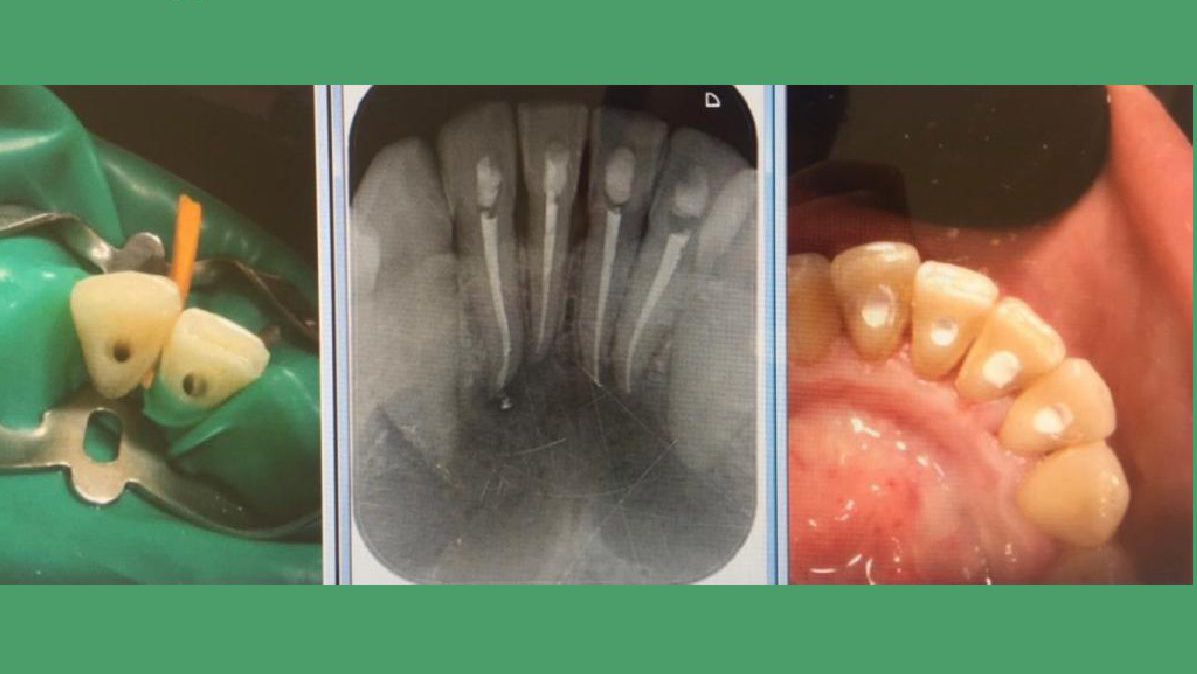

El curetaje dental o raspado, es un procedimiento odontológico en el que se raspa una bolsa de la encía inflamada y se elimina el sarro que se encuentra al interior. Luego se alisa la superficie de la raíz, esto parte de un tratamiento periodontal. Se requiere anestesia local para el procedimiento, por lo que el paciente generalmente no siente ningún dolor.